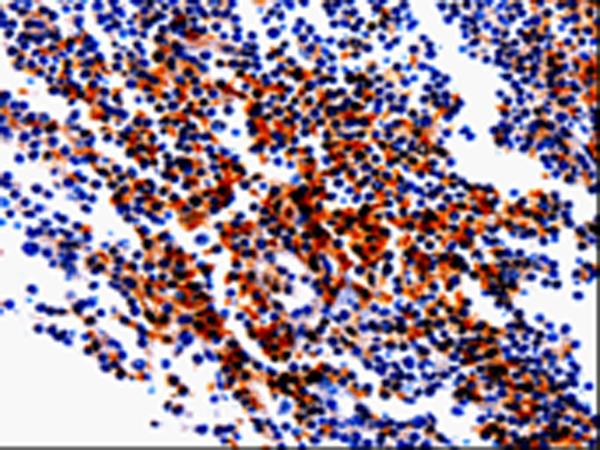

The image is immunohistochemistry of paraffin-embedded Human tonsil tissue using (GDI1 Antibody) at dilution 1/20. (Original magnification: ×200)